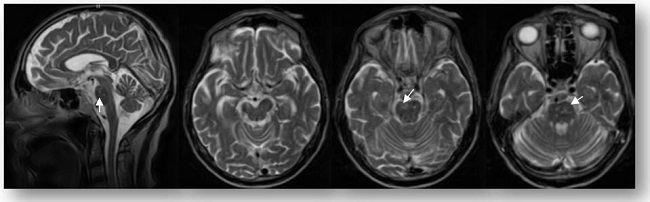

Resonancia Magnética Nuclear (RM) de Cráneo: múltiples lesiones supracallosas en centro oval con imágenes que impresionan dedos de Dawson que irradian de cuerpo calloso (Figura 2), otra mesencefálica derecha en pedúnculo y múltiples imágenes puntiformes en puente. (Figura 3) Atrofia cortical, subcortical y cerebelosa.

Múltiples enfermedades de tipo vascular pueden simular un evento desmielinizante, siendo decisivo el patrón lesional en la neuroimagen. En este caso, la RMN muestra hallazgos típicos de una vasculopatía de pequeños vasos con lesiones en sustancia blanca que predominan en distribución supratentorial frontoparietal, son pequeñas (<3mm) y se extienden más allá de la región periventricular. Además, son evidentes focos de atrofia cortical que pueden ser la huella de áreas de pequeños infartos previos. En cuanto a las lesiones infratentoriales apoya la presencia de un mecanismo vasculopático el hecho de que tienen una predilección central y el área de daño conforma el territorio clásico de distribución arterial.